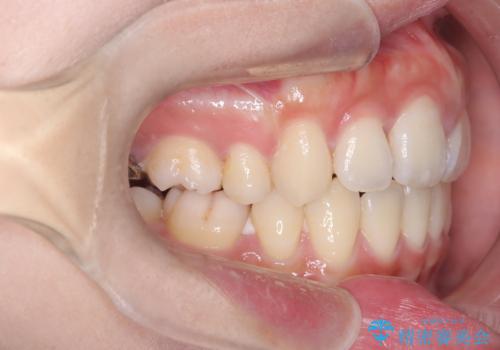

- 口元が出ていること(突出感)を気にされ、これを下げたいという主訴でご来院されました。精密な検査の結果、前歯を大きく後退させ、口元を改善するためには、スペースの確保が不可欠と診断しました。そこで、上下左右の第一小臼歯(4番目の歯)を計4本抜歯し、そのスペースを利用して前歯全体を奥へ移動させる抜歯矯正の治療計画を立案。確実な歯の移動を実現するため、ワイヤー矯正装置を使用しました。

今回の矯正治療では、口元の突出感を解消するためのスペースを確保するため、計画通り上下左右4本の小臼歯を抜歯しました。装置には、確実な歯の移動と細やかな調整が可能なワイヤー矯正を採用。抜歯によってできたスペースを最大限に利用し、前歯を奥へ、そして垂直的に慎重に移動させました。

治療の結果、長年のコンプレックスであった口元の突出感が大幅に解消され、横顔のライン(Eライン)が美しく改善しました。機能的な咬み合わせを確立すると同時に、患者様が望んでいた審美的な口元を獲得していただけました。